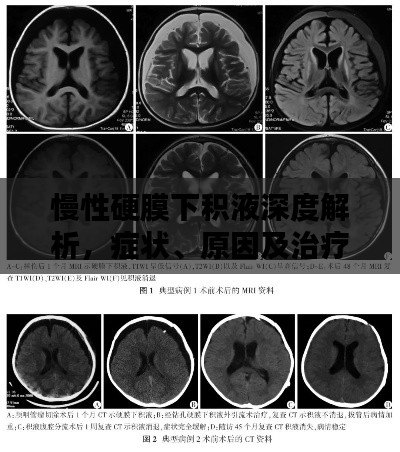

慢性硬膜下积液深度解析,症状、原因及治疗方法